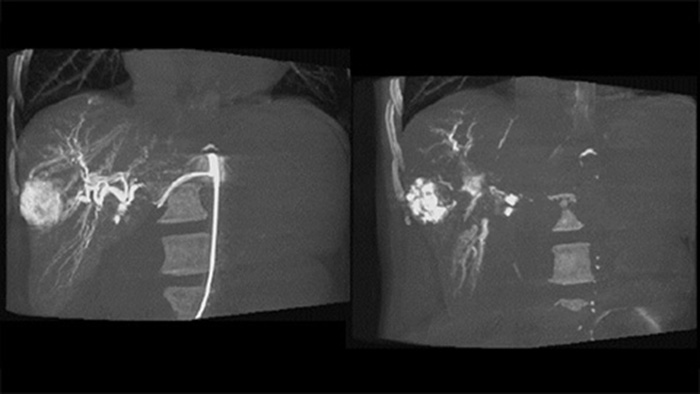

Uma aquisição 3D pós-embolização permite visualizar o depósito alvo de material embólico, como Liopidol ou esferas radiopacas, no tumor.5

A vista dupla permite a visualização simultânea da imagem 3D da fase arterial de pré-embolização e da imagem de pós-embolização para avaliar o ponto final do tratamento.